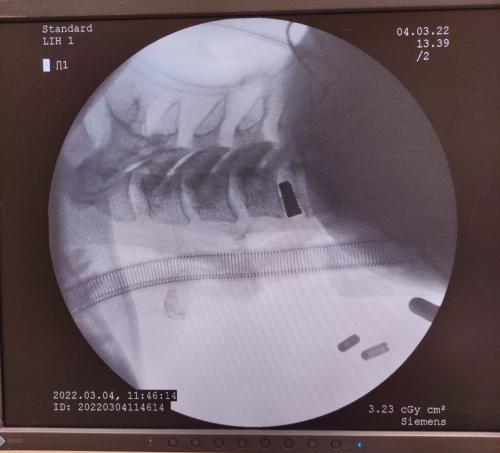

Z satysfakcją informujemy, że w dniu 4.03.2022 r. neurochirurdzy: Marcin Czternastek i Robert Konior wykonali zabiegi operacyjne kręgosłupa techniką minimalnie inwazyjną, z pomocą nowoczesnego mikroskopu operacyjnego.

Zabiegi wykonano u trzech pacjentów, u dwóch z nich usunięto przepuklinę w odcinku lędźwiowym kręgosłupa, natomiast u trzeciego pacjenta usunięto przepuklinę w odcinku szyjnym oraz zastosowano w tym miejscu stabilizację. Wszystkie zabiegi wykonano z niewielkiego nacięcia skórnego (około 4 cm), w powiększeniu mikroskopowym.

Ta technika pozwala na szybki powrót do sprawności. Po kilku dniach pacjenci zostali wypisani do domu - samodzielni, już bez wcześniejszych dolegliwości tj. silnego bólu kończyn.